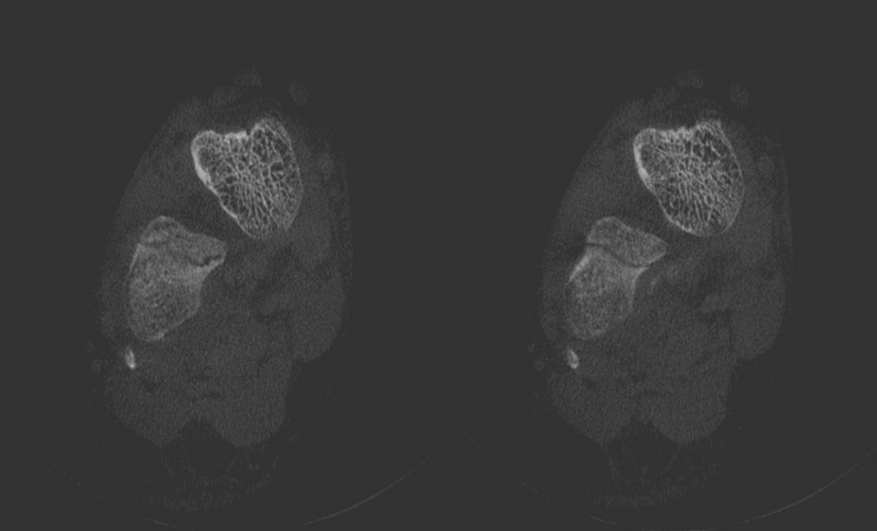

Six weeks later, the patient received a control examination for the healing process. To reduce radiation dose, a CBCT was performed. A thin fracture line of the calcaneus was clearly visible (Figure 4 [Fig. 4]). Some sections indicated ossification signs as proof of a healing process (Figure 4 [Fig. 4]). Hence, there was no need for a surgical approach.

Figure 4: Scans of the calcaneus with a discrete fracture without dislocation of the bone: CBCT taken 6 weeks later at a follow-up examination

CBCT easily detected a discrete fracture in the complex calcaneus. Comparing with CT, the thin fracture was more distinct in the CBCT scans although the fracture was readily in healing process and therefore should be less visible. Consequently, an even distinct imaging of the fracture could be expected by a CBCT scan at initial diagnosis.